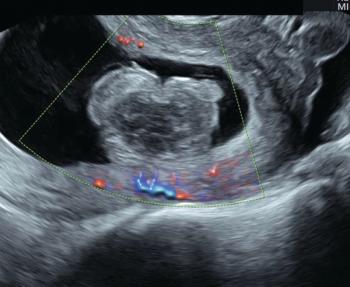

Ultrasound technology can be an indispensable tool for the management of suspected early pregnancy loss.